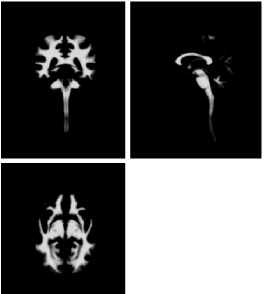

Analogously, in spite of having defined only one gray matter training label, two distinct gray matter classes were introduced in the mixture model (top two rows in Figure 2), to best capture the corresponding distribution of image intensities, which is poorly represented by a single Gaussian component, as opposed to the distribution of white matter intensities. Also in this case, membership probabilities of the labelled training data were computed based on the corresponding intensity values, by making use of equation (15).

The tissue probability maps obtained by applying the modelling framework presented in this paper to the data set described above are depicted in Figure 2. The total number of tissue classes used for this experiment is equal to twelve but three classes, representing air in the background, are not shown.

In particular, Figure 2 shows how one of the two gray matter classes (first row) best fits the subcortical nuclei and also includes voxels affected by partial volume effects at the interface between gray and white matter, while the second one (second row) is more representative of cortical structures, with the presence of partial volume effects generated by the juxtaposition of gray matter and CSF. The third row in Figure 2 shows the white matter class, which also includes most of the brainstem and the spinal cord.

The remaining tissue classes were estimated in a purely unsupervised way. Therefore a non ambiguous anatomical interpretation is not straightforward.

Fat and soft tissues are mainly represented in the last two classes (bottom two rows in Figure 2).

Refer to caption

(a)

Figure 2: Tissue probability maps obtained by applying the presented groupwise generative model to a multispectral data set comprising brain and cervical cord scans of eighty healthy adults, from three different databases.